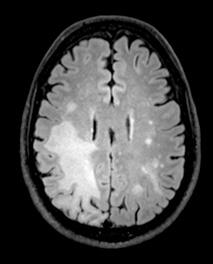

"We found both PD-1 and PD-L1 proteins in the infected parts of brains of patients with PML," said Irene Cortese, M.D., director of the NINDS Neuroimmunology Clinic and first author of the paper. "This led us to ask whether pembrolizumab could be a potential treatment for PML." Eight patients at the NIH Clinical Center, all of whom had signs of worsening PML, were treated with pembrolizumab. The status of their infection was monitored by MRI scans of their brains and by checking the levels of JCV in their cerebral spinal fluid (CSF). In five of the eight patients, the amount of circulating virus was reduced following treatment with pembrolizumab. Importantly, these patients' symptoms improved or stabilized, and their brain MRIs showed shrinking of infection-related brain lesions.